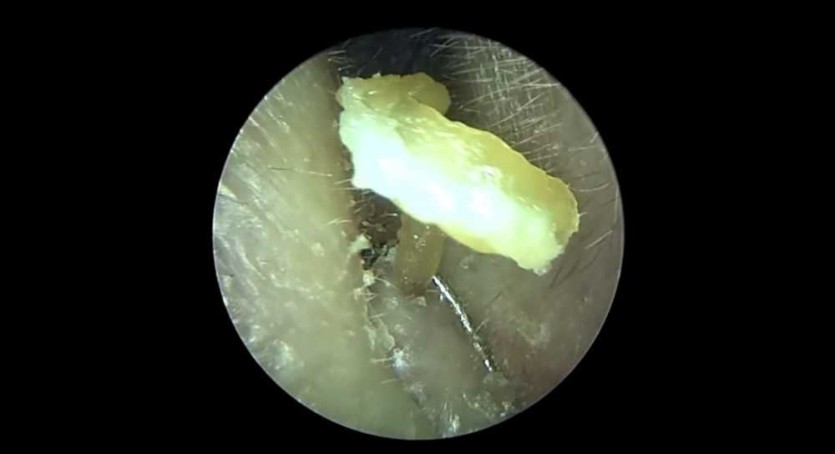

극혐) 귀 입구 왕건이 피지제거 작성자 정보 이단아이유 작성 849 조회 작성일 2025.09.21 04:35 컨텐츠 정보 본문 관련자료 이전 아니 근데 오늘 며칠이냐? 작성일 2025.09.21 06:12 다음 부엌서 관등성명이 절실히 필요한 사람 댓글 (1 ) 작성일 2025.09.21 03:03 댓글 0 등록된 댓글이 없습니다. 로그인한 회원만 댓글 등록이 가능합니다.